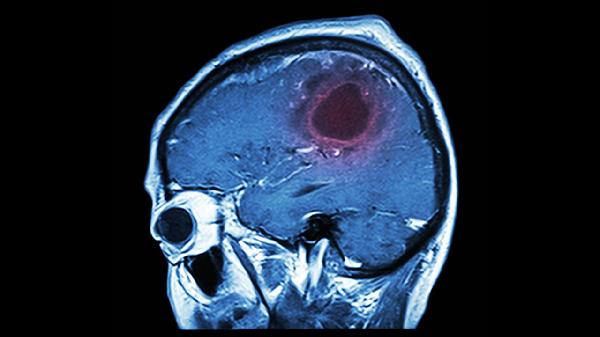

日常需保持适度有氧运动增强血管调节能力,饮食注意补充铁元素和维生素B族。若频繁发作或伴随抽搐、大小便失禁等症状,需进行脑电图、头颅MRI等检查排除癫痫或脑结构性病变。避免驾驶、高空作业等高风险活动,发作后记录时间与诱因有助于医生判断。